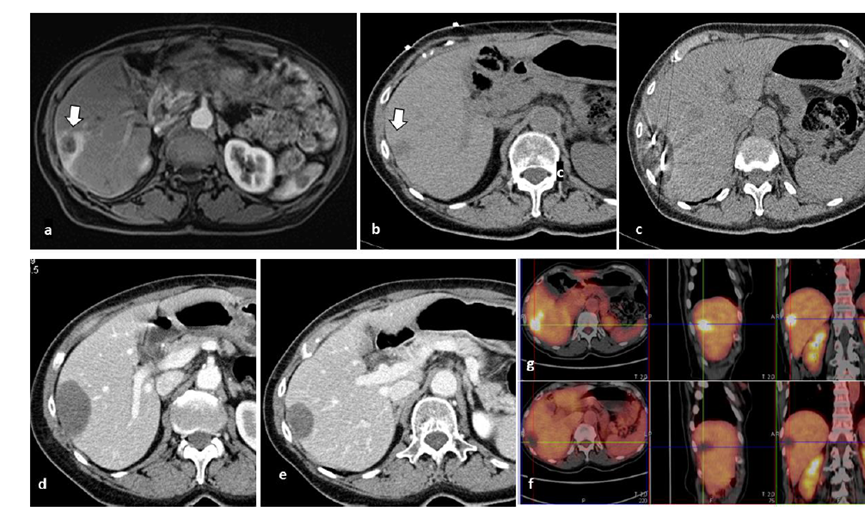

冷凍消融膽囊附近腫瘤病灶

(A)動脈期 MRI 顯示膽囊附近有外周增強病變(箭頭)。

(B)手術過程中 CT 顯示冷凍探針位于病灶內(nèi)。

(C)消融后,術后 1 個月CT 顯示完全消融(箭頭)。

(A)動脈期CT圖像顯示有一個包膜下結節(jié)(箭頭)。(B)門靜脈期CT圖像顯示病灶區(qū)(箭頭)。(C) 在手術過程中的CT顯示一個冷凍探針位于病灶內(nèi)。患者在手術及住院期間無并發(fā)癥及重大并發(fā)癥發(fā)生。隨訪時間中位數(shù)為7個月(范圍:3-12個月),隨訪期間患者無局部腫瘤進展或死亡。

(A)門靜脈期 CT 圖像顯示膽囊附近有病變(箭頭)。(C) 手術過程中CT 顯示冷凍探針位于病灶內(nèi)。(D)消融手術后 1 個月CT 顯示完全消融。

79 歲男性,肝轉移(結直腸癌)腫瘤的完全消融病例

( a ) 軸向 MRI 和 ( b ) 軸向 CT 顯示肝S8段有一個16mm的病灶,鄰近肝緣。( c )冷凍消融期間CT顯示放置了2個冷凍探針,低密度冰球包圍病灶。(d)術后1個月隨訪 CT顯示冰球對應的壞死區(qū)域,未見復發(fā)。(e)術后6個月的CT,壞死區(qū)域縮小,未見復發(fā)。(f)與基線影像(g)相比,12個月后的FDG-PET/CT顯示未見FDG攝取。